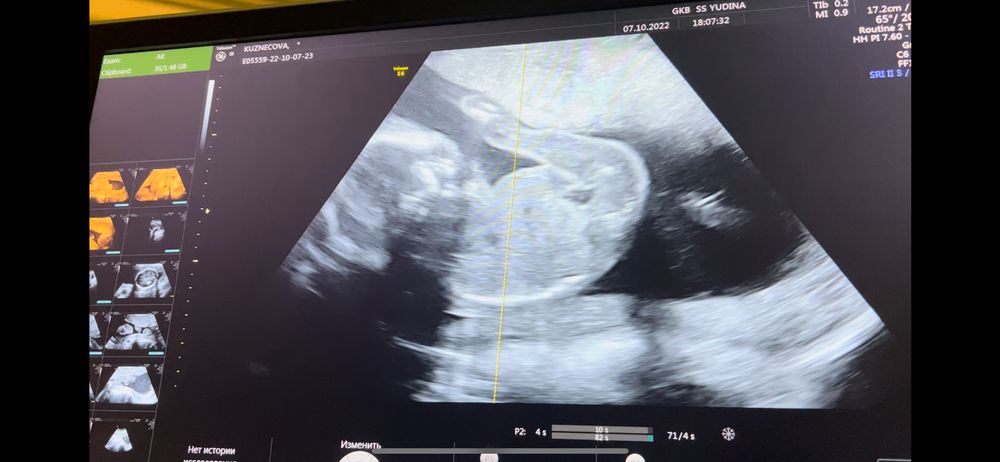

Мой 2 скрининг, 20 недель, ПОЛ, фотопуз✨

Узи делают, смотрю 6а монитор. Отчётливо вижу девочку. Врач,, вам сказать или написать на бумажке пол? ". Я говорю, что хорошо видно девочку... Поздравляю) я тоже больше за девочку была.